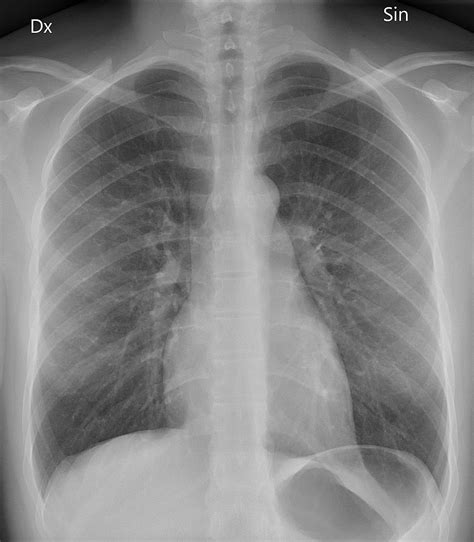

The chest X-ray is one of the most commonly ordered radiologic examinations in medicine, providing valuable information about the lungs, heart, and surrounding structures. A normal chest X-ray can be an indicator of good respiratory health, but interpreting these images requires a comprehensive understanding of what constitutes “normal” and how various factors can influence the appearance of the X-ray. Here are five key ways a normal chest X-ray can be assessed, emphasizing the importance of a thorough and nuanced interpretation:

A critical aspect of assessing a chest X-ray is evaluating the cardiothoracic ratio, which is the ratio of the widest diameter of the heart to the widest diameter of the chest (from one inner edge of the rib cage to the other). Normally, this ratio should be less than 0.5. An increased cardiothoracic ratio can indicate cardiomegaly (enlargement of the heart), which might suggest various cardiac conditions. In a normal chest X-ray, the heart size should be appropriate for the patient’s body size, and this ratio can provide a quick and useful indicator of cardiac health.

The lung fields should appear clear and dark on a normal chest X-ray, indicating the absence of consolidation or other pathologies. The lung parenchyma, which includes the alveoli, bronchioles, and capillaries, should not show any signs of disease such as opacities, nodules, or cavitations. The presence of any abnormalities in the lung fields can suggest a wide range of conditions, from infections to chronic diseases like emphysema. Thus, a thorough examination of the lung fields is essential for determining the normalcy of a chest X-ray.

The pleural spaces, which are the areas between the lungs and the chest wall, should not contain any significant amount of fluid or air (other than what is considered normal). The costophrenic angles, where the diaphragm meets the rib cage, should be sharp and well-defined. Blunting of these angles can indicate pleural effusion, a condition where excess fluid accumulates in the pleural space, which can be a sign of various diseases, including infections, malignancies, and heart failure. A normal chest X-ray will show clear, unobstructed costophrenic angles.

The diaphragm, the major muscle used for breathing, should be at an appropriate level and have a normal contour on a chest X-ray. The position of the diaphragm can be influenced by factors such as lung volume and gravity. In a normal inspiratory chest X-ray, the diaphragm should be at or below the 10th rib anteriorly and the 6th rib posteriorly. Abnormalities in diaphragmatic position or contour can suggest conditions affecting the lungs or the diaphragm itself. Moreover, assessing the movement of the diaphragm during breathing (through fluoroscopy or video X-ray) can provide additional insights into respiratory function.

Finally, a normal chest X-ray should also show a normal bony thorax and soft tissues. The bony structures, including the ribs, vertebrae, and sternum, should appear intact without any fractures or lesions. The soft tissues of the chest wall, including the breasts and the muscles, should not show any signs of disease such as masses or thickening. The mediastinum, which contains the heart, trachea, esophagus, and other vital structures, should be of normal width and density, as an enlarged mediastinum can indicate serious conditions like lymphoma or aortic aneurysm.

Interpreting a chest X-ray as “normal” requires a detailed examination of various anatomical structures and an understanding of how different conditions can affect the appearance of these structures on the X-ray. The cardiothoracic ratio, lung fields, pleural spaces, diaphragmatic position, and the bony thorax and soft tissues all play critical roles in assessing the normalcy of a chest X-ray. Healthcare professionals must consider these factors in the context of the patient’s overall health and clinical presentation to provide an accurate interpretation and appropriate follow-up care.